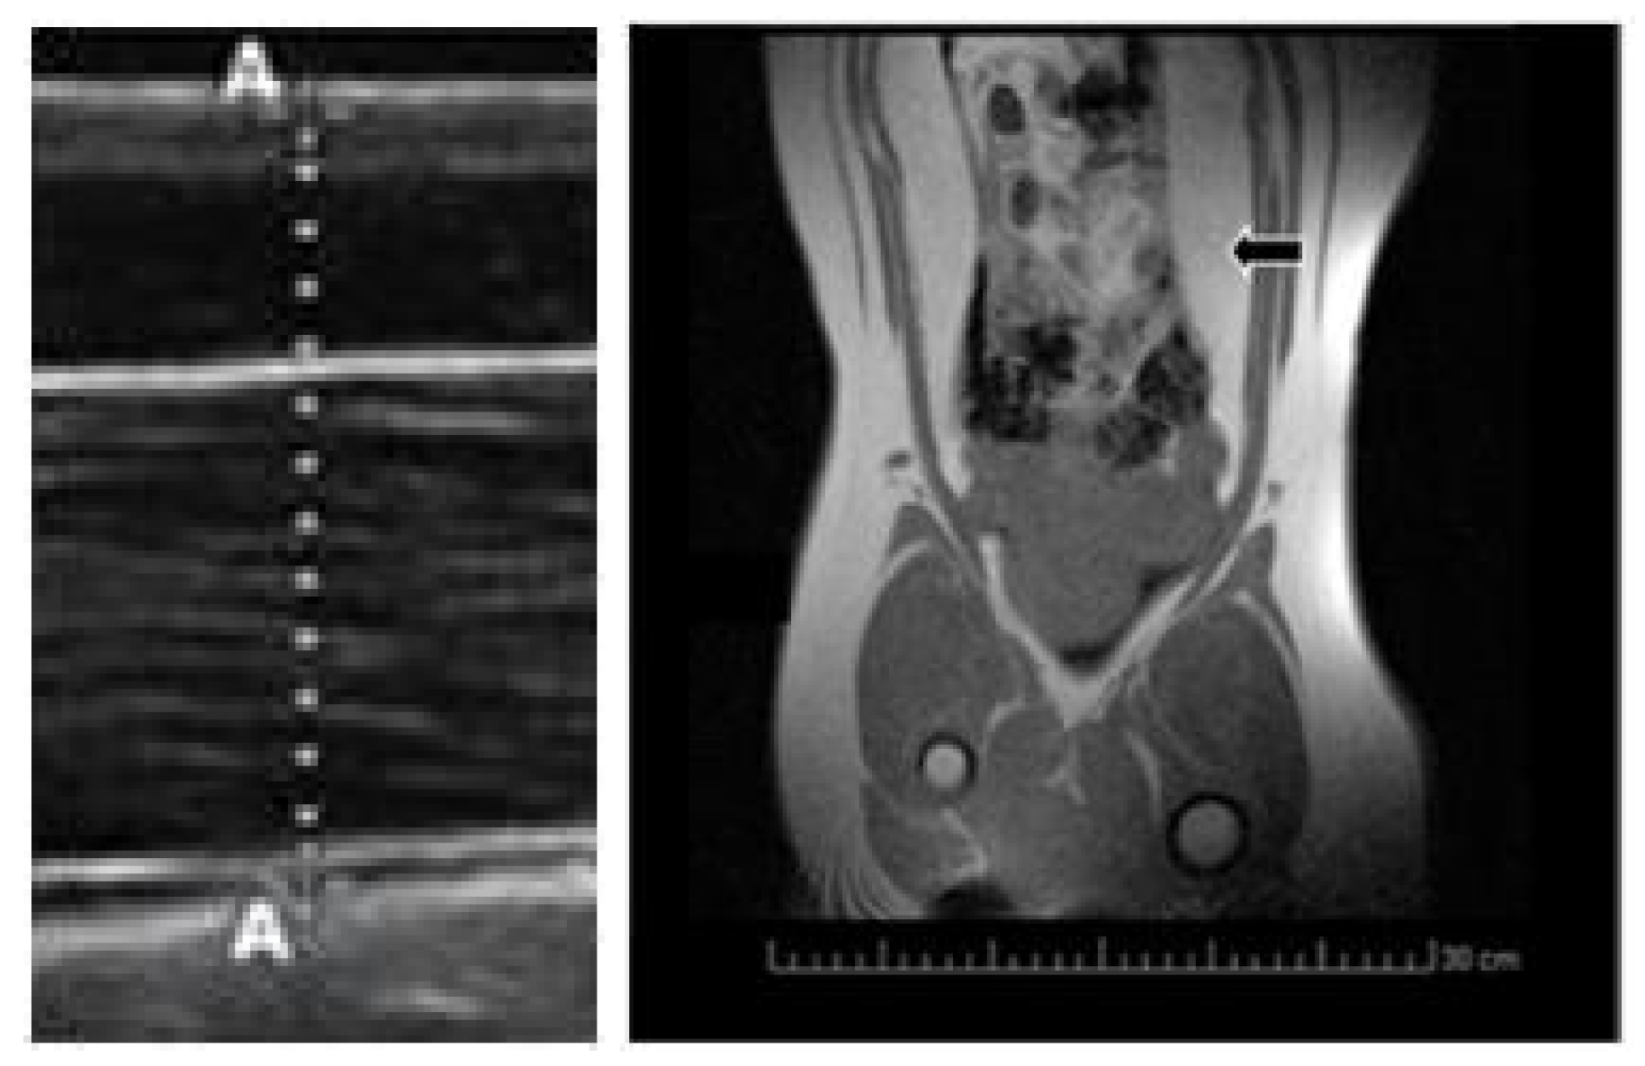

| Visceral Fat Depot (cm2) | 31.2 ± 5.3a | 18.3 ± 3.4b | 17.2 ± 4.1b |